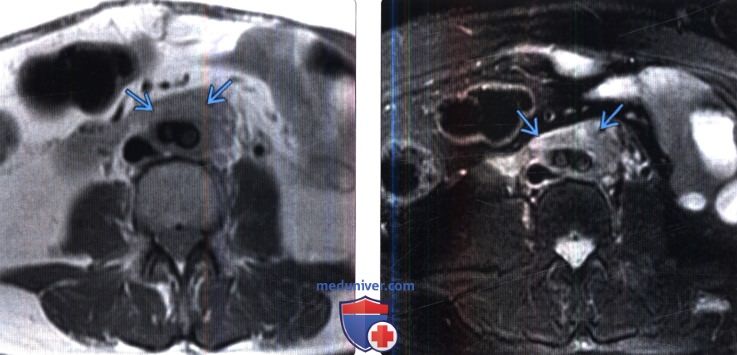

КТ ретроперитонеального фиброза: Изображения и диагностика